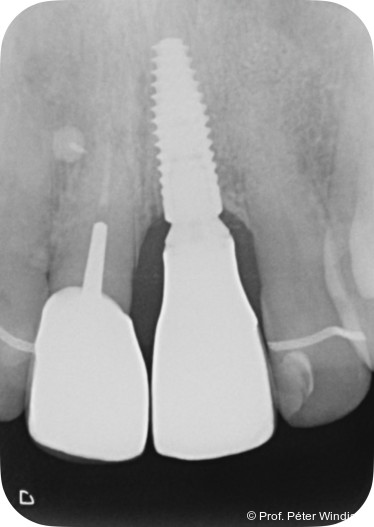

Das Weichgewebe präsentierte sich klinisch entzündungsfrei. Radiologisch zeigte sich nach zwölf Monaten eine deutliche Verbesserung der knöchernen Situation im Sinne einer Auffüllung des knöchernen Defekts (Abb. 12). Das Ergebnis konnte durch regelmäßige Implantat-Maintenancetermine stabilisiert werden. Abbildung 13 zeigt die ausgereifte periimplantäre Hartgewebesituation.